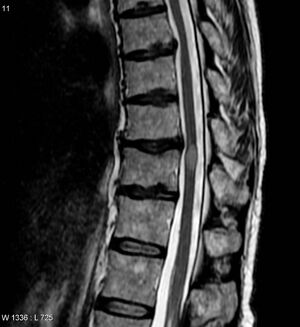

| MRI image of transverse myelitis patient's spinal cord | |

التهاب النخاع Myelitis مرض يصيب النُخاع الشوكي أو نقي العظم. وغالبًا ما يُسببه فيروس، أو عدوى أخرى. والتهاب سنجابية النُخاع هو أحد الأشكال الأخرى لالتهاب النخاع، وكذا التصلب المتعدد، وداء الكلب. وغالبًا ما تشمل أعراض أمراض التهاب النخاع آلام الظهر والشلل. Myelitis is classified to several categories depending on the area or the cause of the lesion; however, any inflammatory attack on the spinal cord is often referred to as transverse myelitis.